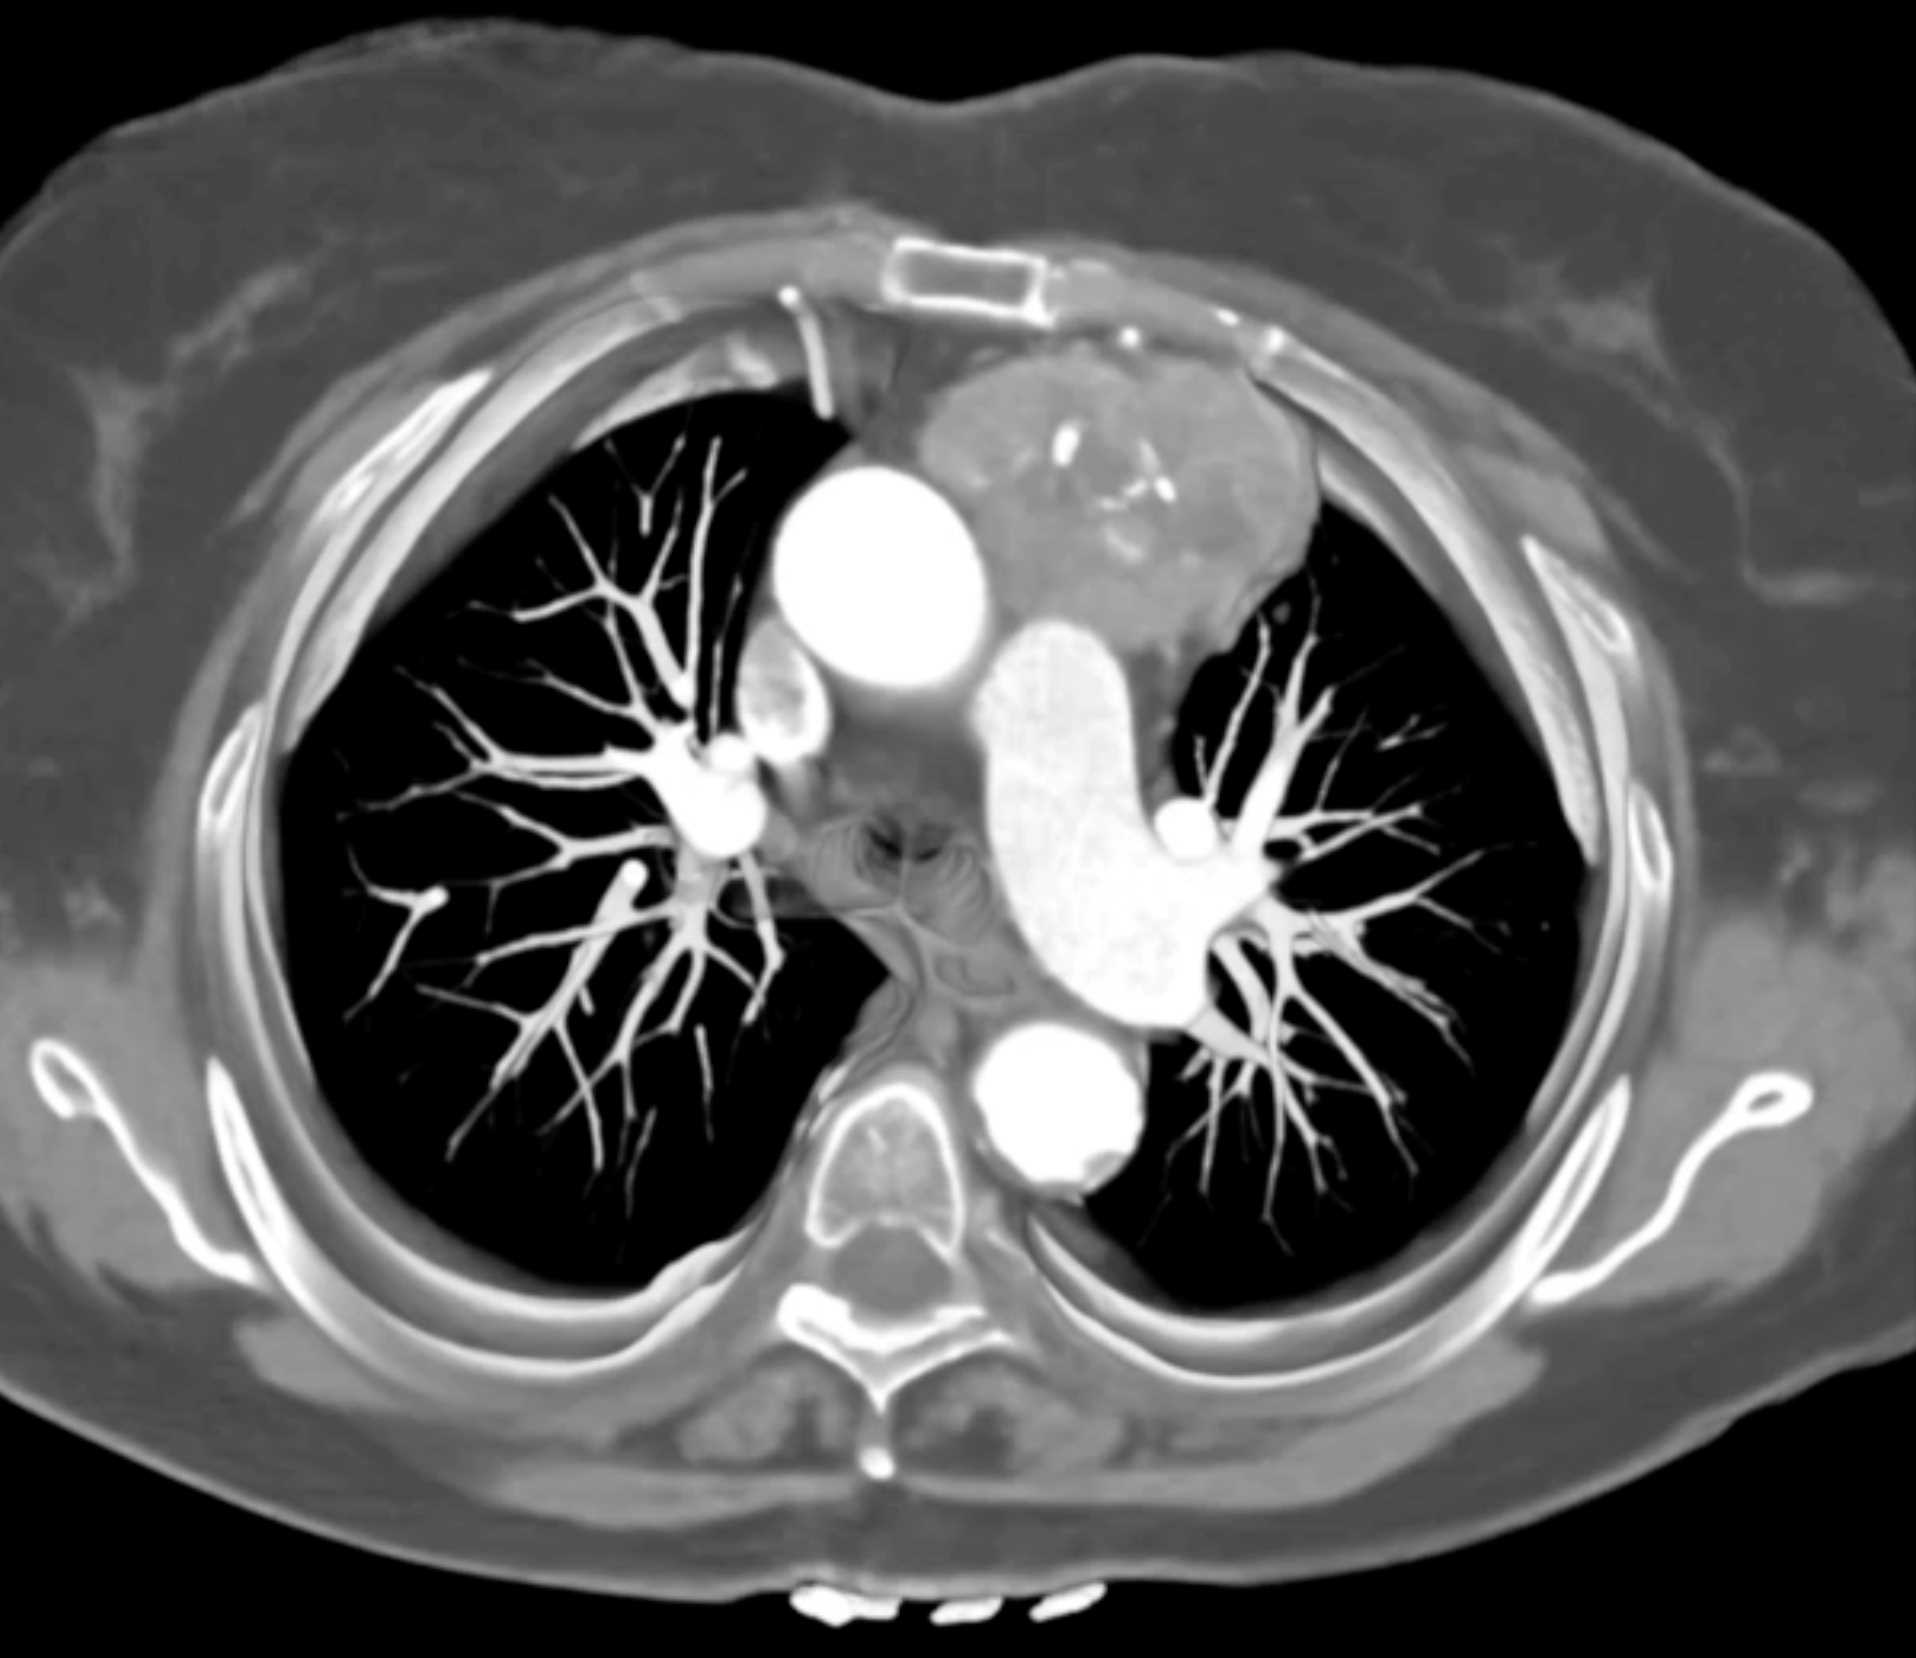

Thymic Carcinoma